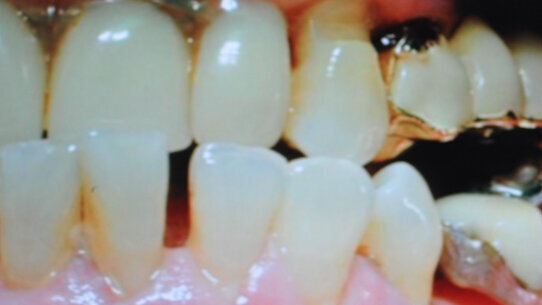

È stato esaminato il caso di una paziente di sesso femminile di 60 anni, con un quadro morfo-funzionale stomatognatico caratterizzato da grave deficit strutturale per la presenza di una protesi rimovibile scheletrata superiore incongrua, con morso inverso anteriore e sovraccarico funzionale in occlusione abituale (non in relazione centrica), causa di un trauma occlusale cronico.

Nei settori latero-posteriori non esiste appoggio occlusale stabile (Figg. 1, 3).

Il quadro parodontale evidenzia in corrispondenza del settore antero-inferiore, da 4.3 a 3.3, flogosi settico-batterica con edema e congestione da stasi, in particolare a carico delle papille.

Il sondaggio evidenzia lesioni dell’attacco epiteliale e sanguinamento, atrofia della cresta ossea-alveolare e mobilità dentale di grado 1-2.

La diagnosi conseguente è malocclusione dento-protesica con sovraccarico funzionale anteriore da precontatto dislocante distale (Figg. 2a, 2b), difetto occlusale latero-posteriore bilaterale, sofferenza gengivo-parodontale, e flogosi cronica ed edema congestizio da stasi, conseguente alla disfunzione biomeccanica con sovrapposizione di quadro infettivo batterico.

Significativo l’aspetto del riallineamento dentale del gruppo 4.3-3.3 (dopo la riabilitazione protesica), non più sollecitato dalla pressione traumatica del morso inverso preesistente (Figg. 4a, 4b, 5). Il monitoraggio del profilo batterico è stato eseguito secondo la tecnica del campione in vivo e conta batterica mediante microscopia a contrasto di fase (Fig. 6), e il significato clinico dei riscontri di tali profili è stato considerato in relazione alle indicazioni di Listgarten per quanto riguarda il significato clinico e prognostico27. Durante il periodo di osservazione sono state eseguite anche sedute di igiene professionale con rimozione della placca dento-gengivale.